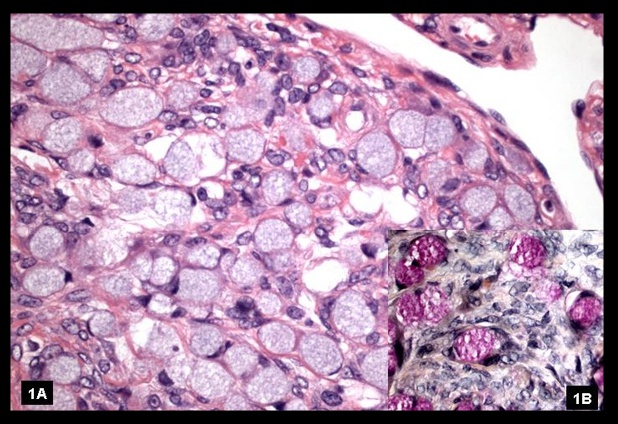

_Histology will reveal cells with abundant lipid-filled cytoplasm. Grossly these are solid, yellow appearing tumors.,

Thecoma of the ovary: